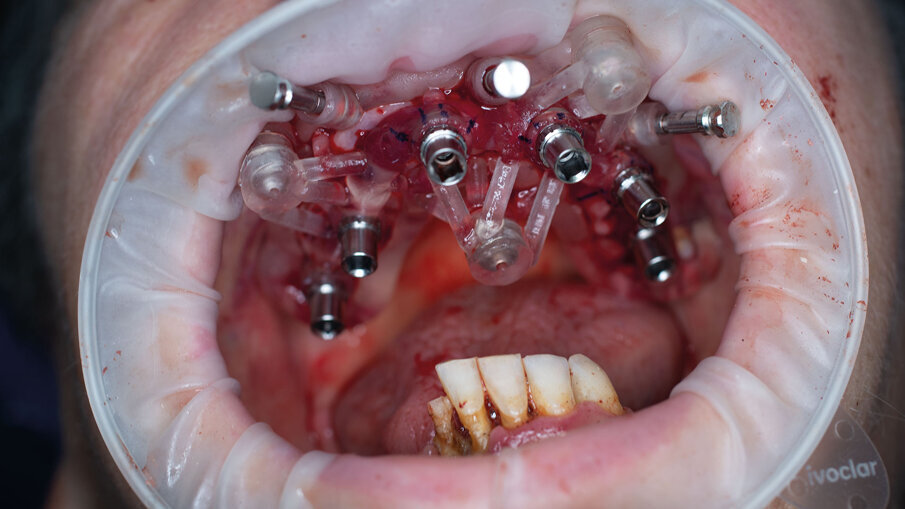

Per la realizzazione delle dime chirurgiche abbiamo utilizzato il nuovo modulo Sculpt rilasciato per lo stesso software di chirurgia guidata BNX 3D GUIDE. Questo nuovo modulo permette di creare una serie di dime scomposte da utilizzare in sequenza per eseguire le estrazioni e l’osteoplastica necessaria, rimanendo sempre all’interno di un flusso di lavoro guidato. Le dime si adattano l’una all’altra grazie a supporti di accoppiamento che contengono piccoli magneti con polarità opposta. L’azione di questi magneti permette di ritrovare velocemente e fedelmente sempre la stessa posizione delle dime anche se dovessimo rimuoverle per poi reinserirle. Affidandoci alla stabilità ancora presente su alcuni denti abbiamo progettato una prima dima ad appoggio dentale che permettesse il corretto posizionamento della dima esterna che sarà l’unica a rimanere sempre in posizione fino alla fine dell’intervento (Fig. 9). Una volta stabilizzata con i pin di stabilizzazione e rimosso il posizionatore, si è potuto apprezzare la bellezza della metodica che permette un’ampia visione e molto spazio a disposizione per poter eseguire le fasi chirurgiche preliminari di preparazione (estrazioni e sollevamento di piccoli lembi). Liberata l’arcata dall’ingombro dei denti e di tessuti in eccesso si è potuto posizionare la dima di perforazione nella corretta posizione grazie alla presenza della dima esterna rimasta in posizione (Figg. 10-13).

Alla preparazione dei tunnel implantari è seguito il loro inserimento sempre con tecnica guidata utilizzando gli appositi montatori forniti nel kit, avendo cura di far combaciare le tacche di riferimento dei montatori con le linee di repere preventivamente disegnate sulla dima così da ottenere il corretto posizionamento dei 2 mua angolati previsti nel settore anteriore (Fig. 14). In fase chirurgica il posizionamento dei mua è stato ulteriormente facilitato dalla presenza di un doppio esagono presente all’interno dell’impianto che rende possibili ulteriori aggiustamenti “di fino” del componente protesico. Avvitate tutte le torrette il provvisorio è stato poi cementato con cemento duale dedicato utilizzando un foglietto di diga preforato per facilitarne la cementazione (Figg. 15, 16).